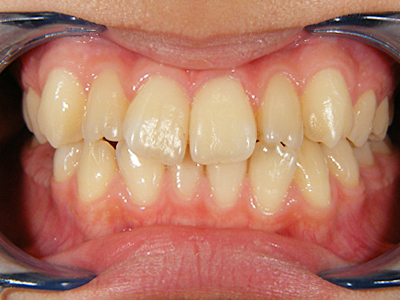

1. 術前正面

この患者様は幼児期から私が拝見している女の子の患者様です。乳歯交換期を終える段階の正面観です。上顎左右3,3番(犬歯)右上1番の中切歯の捻転が著明です。下顎に関しては、右下1番の舌側転位。左下2,3番間の叢生が著明です。正中もそれなりにずれています。